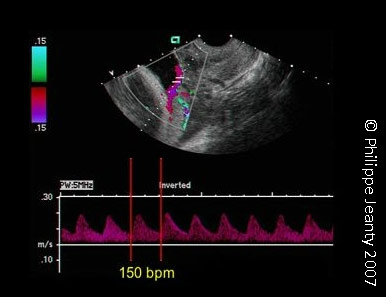

Vasa Praevia confirmed by Colour Doppler ultrasound (note the fetal pulse at 150bpm)

Courtesy and © 2007 www.thefetus.net